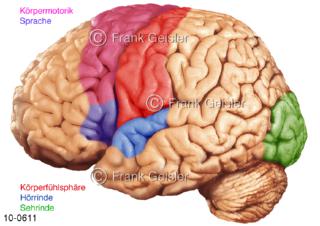

Bildergalerie Nervensystem

Bilder zum Nervensystem,dem Gehirn, Teil des zentralen Nervensystem, Zentralnervensystem ZNSmit Rückenmark, Abbildungen zum Nervengeflecht (Nervenplexus), die Verflechtungen von Nervenfasern, aus der Wirbelsäule hervortretende Nervenäst sowie Nervenzellen der Nerven